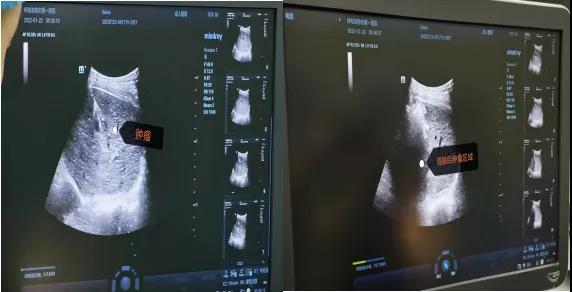

病例2. 患者,男,63岁,因上腹部憋胀不适1月余入院,患者入院前已经辗转区内多家医院诊治。术前评估检查全腹增强CT:肝硬化,脾切除术后,肝S6段小肝癌,肿瘤直径约2cm;甲胎蛋白15.05ng/ml。肿瘤位于肝脏右后叶,位置深,腹腔镜手术操作因合并基础疾病及手术史,恐无法受益。因选择消融治疗具有对肝功能影响少,创伤小,疗效确切的特点。经团队讨论后决定行消融治疗,于2022年1月22日在外院专家指导下,全麻超声引导行肝肿瘤射频消融术。消融治疗主要适用于CNLC Ia期及部分Ib期肝癌(即单个肿瘤、直径≤5cm,或2-3个肿瘤最大直径≤3cm无血管、胆管和邻近器官侵犯及远处转移,可获得根治性治疗效果)。术后患者肝功能恢复正常,无并发症痊愈出院。